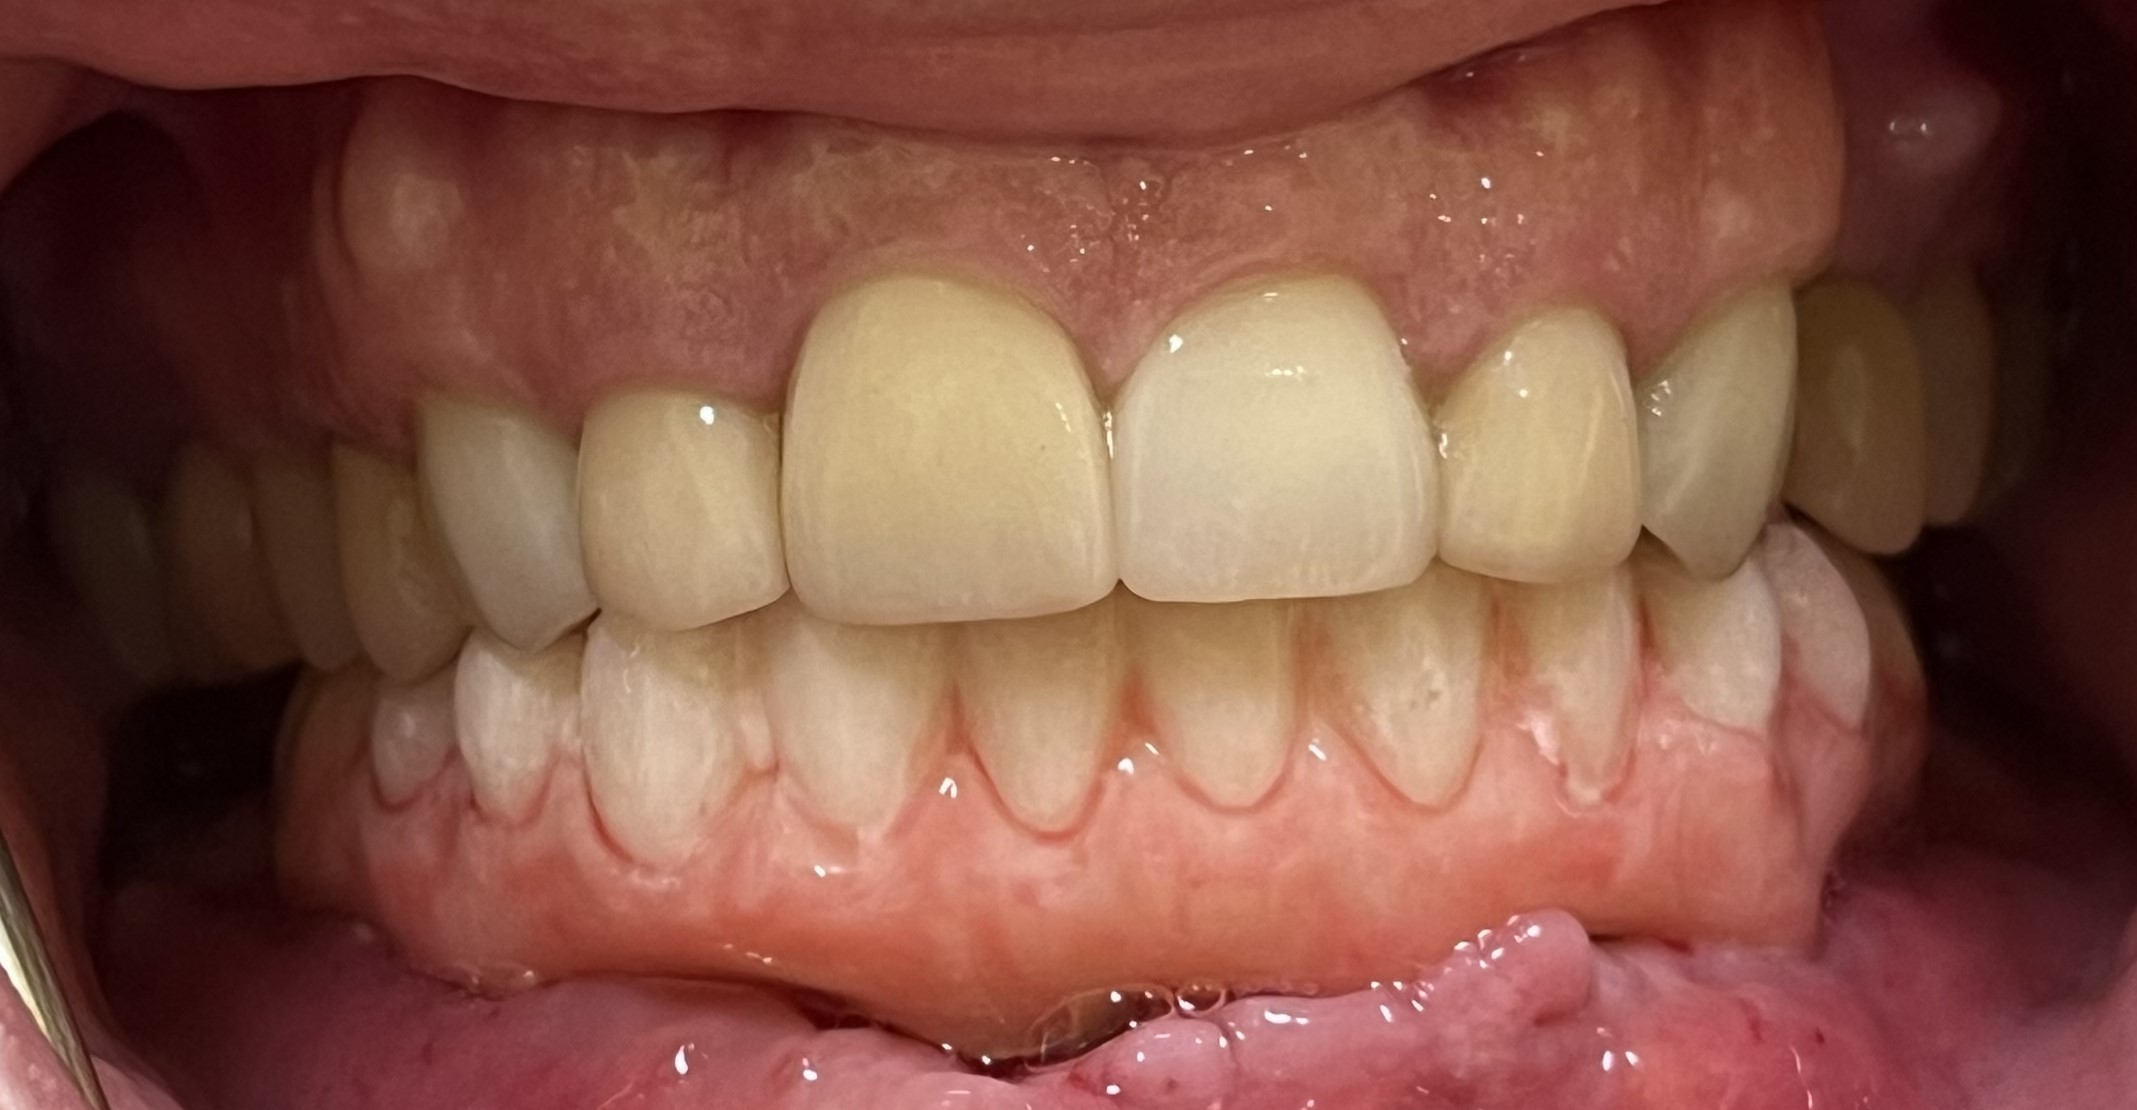

- Natural-looking, confident smiles

- Stronger bite force and better chewing ability

From improved comfort to restored self-confidence, the long-term advantages of All on X implants truly change lives.